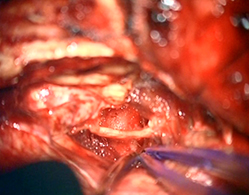

< 手術所見 >

腫瘍消失、顔面神経麻痺なし